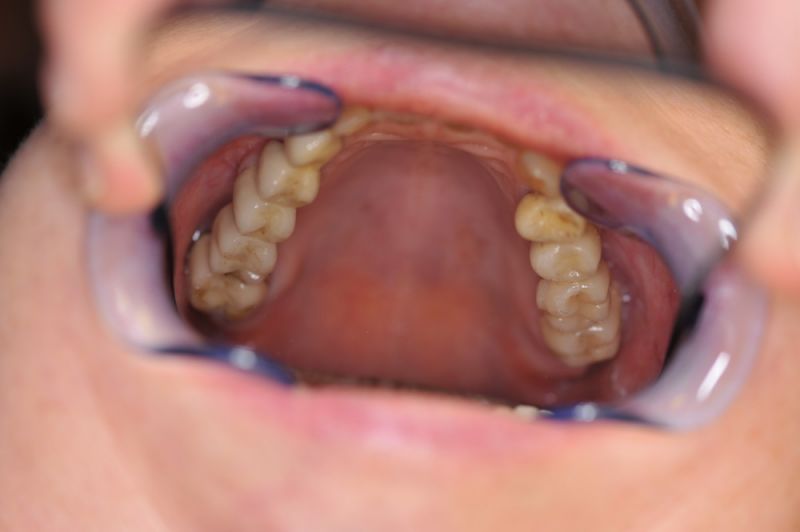

Es war eine Kombination aus Schmerzen bis an die Suizidgrenze, beschränkten wirtschaftlichen Möglichkeiten, sehr stark eingeschränkten Möglichkeiten der für Implantate zur Verfügung stehenden Knochenverhältnisse in einem stark atrophierten Unterkieferseitenzahnbereich und zudem dann auch noch durch auftretenden Problemen bei der Implantatinsertion und nachfolgenden Versorgung der Implantate.

Alle 3 Monate Recall! Das ist jetzt Pflicht für diese Patientin und zwar so lange, so lange sie mit dieser Arbeit durch die Gegend laufen möchte! Und eiserne Disziplin bei der Mundhygiene!